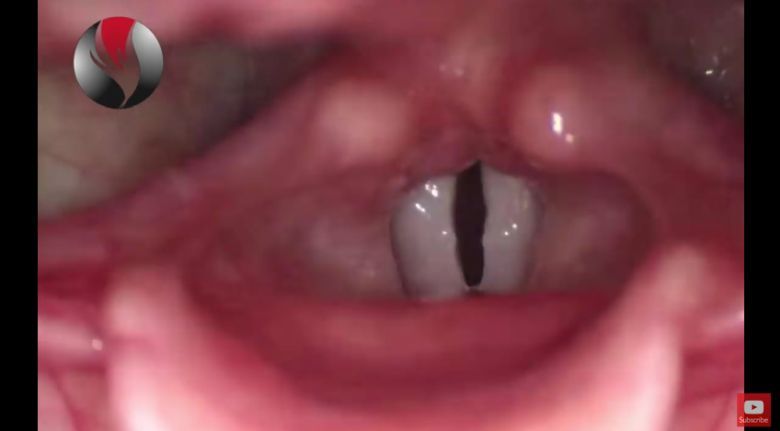

Jak działa ludzki głos? (wideo HD)